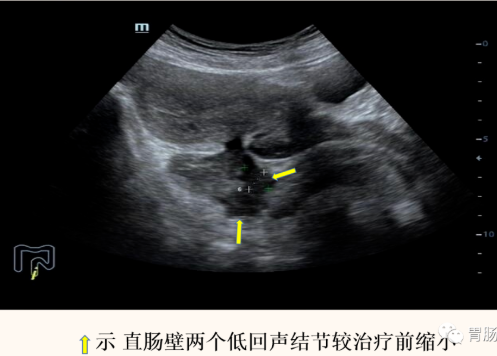

化疗后1周复查(2022-01-18日)超声示:

直肠后壁及右侧壁低回声结节明显减小,部分小结节已不能清晰显示,仅可见两个低回声结节,大小分别约2.1x1.1cm,1.5x1.1cm,直肠壁稍厚,厚约0.6cm,粘膜面直肠溃疡变浅,直肠无明显狭窄。患者自述大便顺畅无不适。

造影剂经直肠顺利通过,肠腔已无明显狭窄。